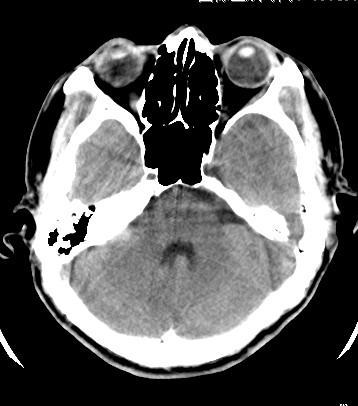

标题: CT17787:头ct,请帮忙看看右顶部有无异常 [打印本页]

标题: CT17787:头ct,请帮忙看看右顶部有无异常

男,58岁,偶有头疼

未见明显异常。右顶部低密度影为深入的脑沟。

增宽的脑沟!无异常!

是宽大的脑沟,局部不象有萎缩现象

增宽的脑沟

诊断依据:

低密度影周围脑组织边缘均有一层脑灰质覆盖。

正常啊,是对右顶增宽脑沟有疑问吗